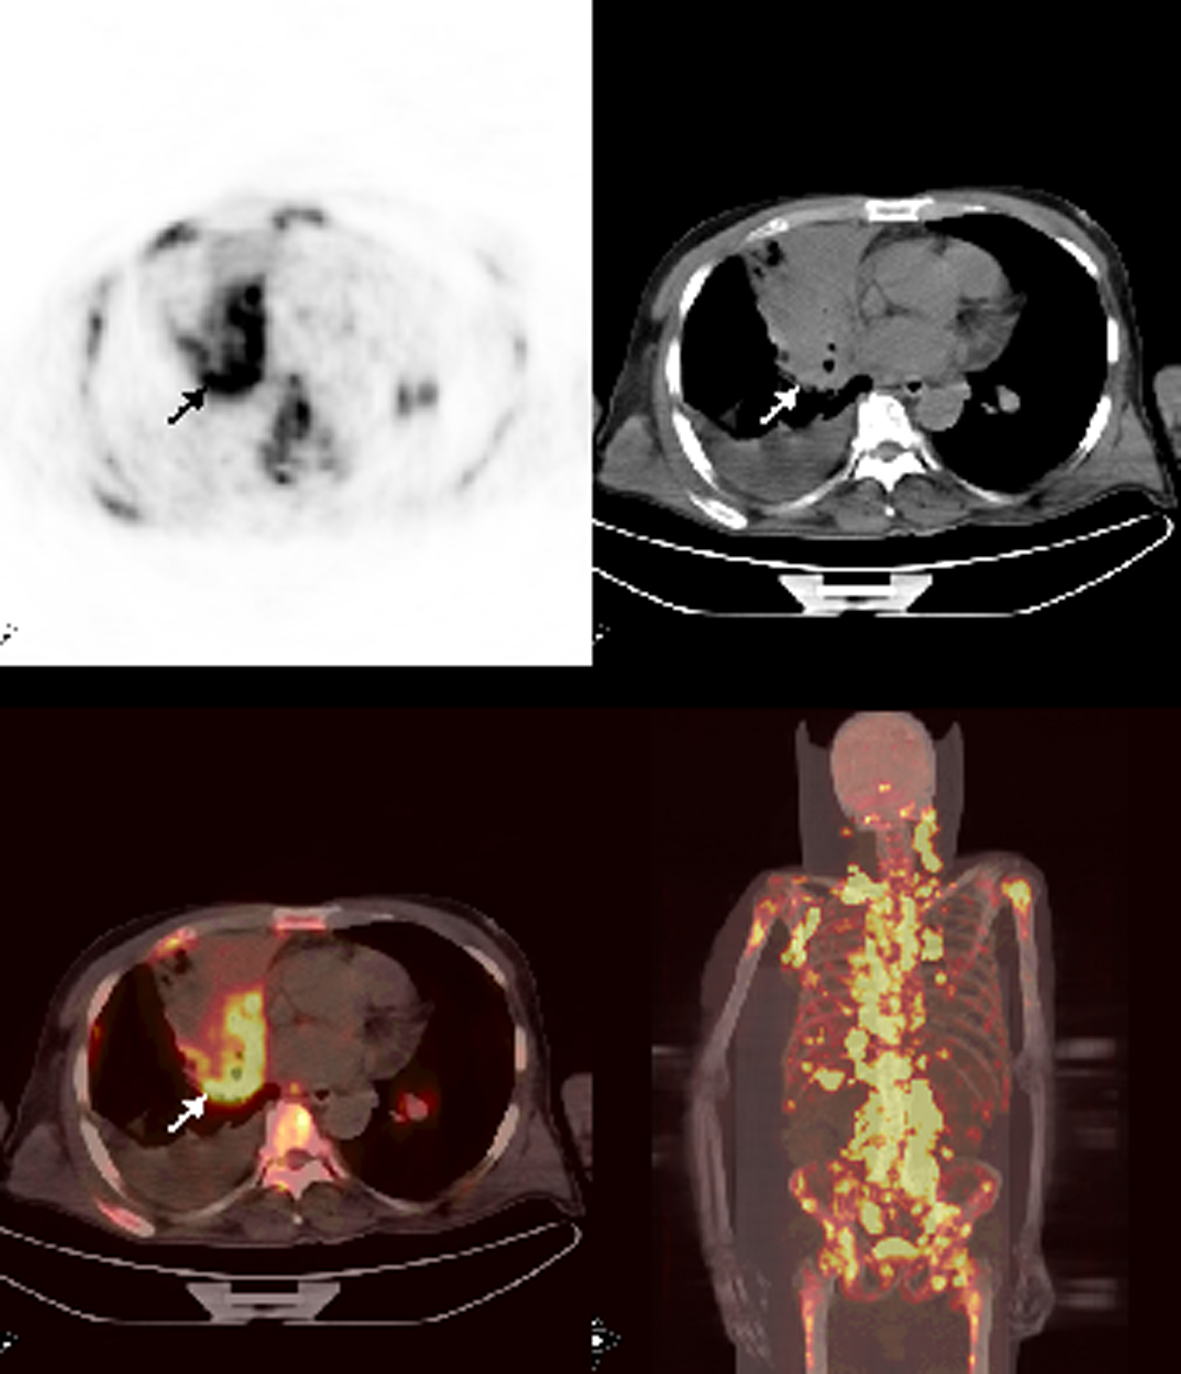

Patient 10

A 62-year-old male patient with history of chronic lymphocytic leukemia presented with cough, shortness of breath, cervical lymphadenopathy and sweating for the last 3 months. A cervical excisional biopsy showed undifferentiated carcinoma and infiltration with small lymphocytes consistent with chronic lymphocytic leukemia. A PET/CT which was ordered for staging and detection of primary tumor revealed hypermetabolic mass at the right hilar region. Also, metastatic bilateral cervical, supraclavicular, bilateral axillary, abdominal, pelvic lymphadenopathies in addition to multiple liver and widespread bone marrow metastasis were detected (Fig. 5). Although complete blood count was normal, diffuse bone marrow involvement prompted us to attempt a bone marrow biopsy. Biopsy showed poorly differentiated large cell carcinoma of the lung.

![]() Click for large image | Figure 5. Axial and MIP PET/CT images showed a mass at the right hilar region with very intense FDG accumulation. There were also multipl bone-bone marrow metastases and extraskeletal metastases with prominent FDG uptake. |